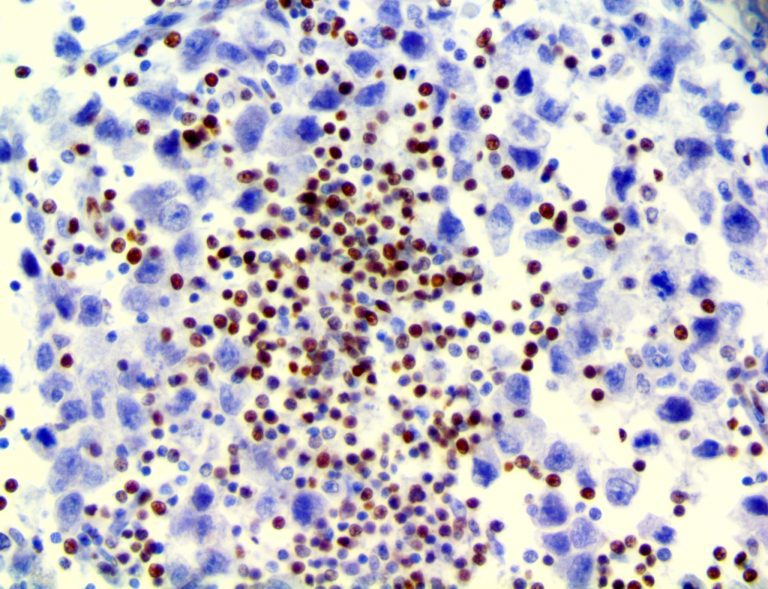

It is the ICU physician who is most likely to witness one of the deadliest manifestations of the abnormal immunological response, the cytokine storm syndrome (CSS). This response is also referred to by some as the cytokine release syndrome (CRS). CSS is characterized by continuous activation and expansion of macrophage and lymphocyte populations, which secrete large amounts of cytokines, causing the cytokine storm. This massive cytokine release is akin to hemophagocytic lymphohistiocytosis (HLH) disease, a syndrome characterized by initial unchecked and persistent activation of cytotoxic T lymphocytes and NK cells.

Clinical and laboratory manifestations of HLH include fever, enlarged liver and/or spleen, neurologic dysfunction, coagulopathy, liver dysfunction, cytopenias (i.e., low levels of erythrocytes, leukocytes, and/or platelets), hypertriglyceridemia, hyperferritinemia, hemophagocytosis, and eventually diminished NK cell activity as the immune system becomes progressively paralyzed. HLH can be familial (primary HLH) or secondary to another disease process (sHLH), such as rheumatic disease, in which it is referred to as macrophage activation syndrome (MAS, characterized by elevated ferritin).